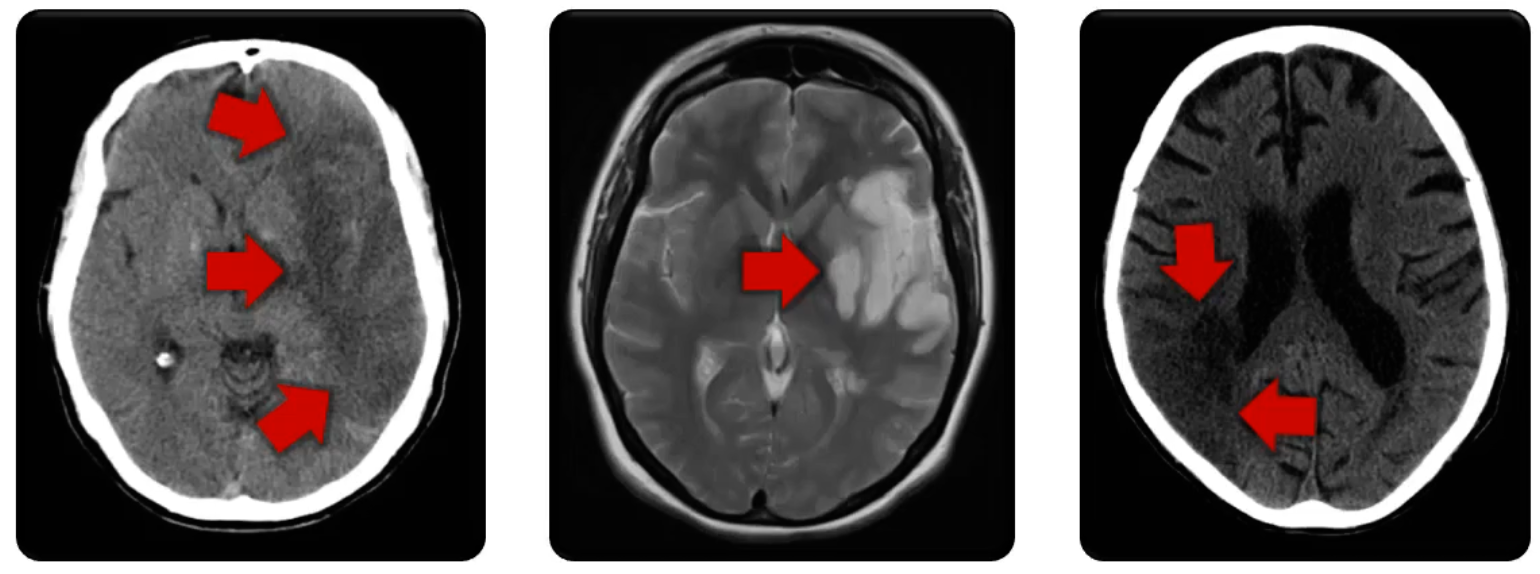

Subarachnoid Hemorrhage

Subarachnoid bleeding around the Circle of Willis

Caused by ruptured aneurysm

Subarachnoid Hem.

Intracranial Hem.

Hemorrhage stroke

ruptured vessels

Can result in edema, mass effect, and limited blood supply

Traumatic Contusions

Intracranial bleeding

caused by trauma

can appear with other hemorrhage injuries

can cause neurologic deficits